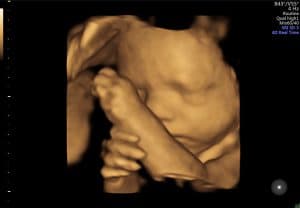

Nadat de baby met een 2D echo in beeld is gebracht en de ligging duidelijk is, wordt er met een 3D echo extra kleur aan de doorsnede toegevoegd. Je ziet dan drie dimensies (3D), namelijk lengte, breedte en diepte. Waar je met een 2D echo als het ware door je kindje heen kijkt, kijk je er met een 3D echo omheen. Dus alles wat bijvoorbeeld voor het gezichtje van de baby ligt is met een 3D echo wel te zien. Door de 3D beelden te combineren met 4D echografie, krijg je bewegende 3D beelden. Dit maakt het een ‘live’ ervaring om naar je kindje te kijken.

De foto’s die je vaak op internet ziet en ook op deze site zijn optimale beelden. Dan bedoelen we een zeer gunstige ligging van de baby, slanke zwangere en mogelijk niet de eerste zwangerschap, waardoor de wand van de baarmoeder soepeler is. Zie deze foto’s dus niet als vergelijking voor je eigen 3/4D-echo.